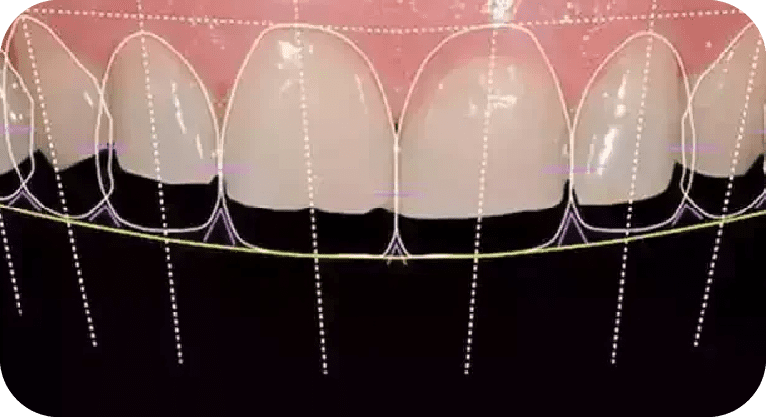

Paciente femenino, “29” años

Tratamiento: Carillas dentales

El paciente acudió a la clínica dental por inconformidad con la forma y posición de sus dientes. Tras una evaluación personalizada, se realizó un diseño de sonrisa con carillas dentales para mejorar su estética dental, logrando resultados naturales y satisfactorios.

Paciente masculino, “33” años

Tratamiento: Diseño de sonrisa

El paciente presentó inconformidad con la estética de sus dientes anteriores. Tras un diagnóstico clínico y análisis digital, se realizó diseño de sonrisa con carillas de porcelana para corregir forma, posición y tamaño dental, logrando una apariencia armónica y natural que cumplió con sus expectativas estéticas.